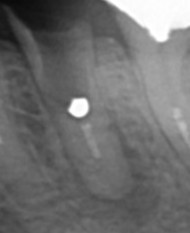

現状 左下5番が残根状態で根尖部が腫脹、自発痛を訴えている。根管内を肉眼で目視すると除去できなかったと思われるメタルコアーが残っているのが確認できる。

【残根、いわゆるC4状態】

【根管内底部に金属が光っているのが分かる】